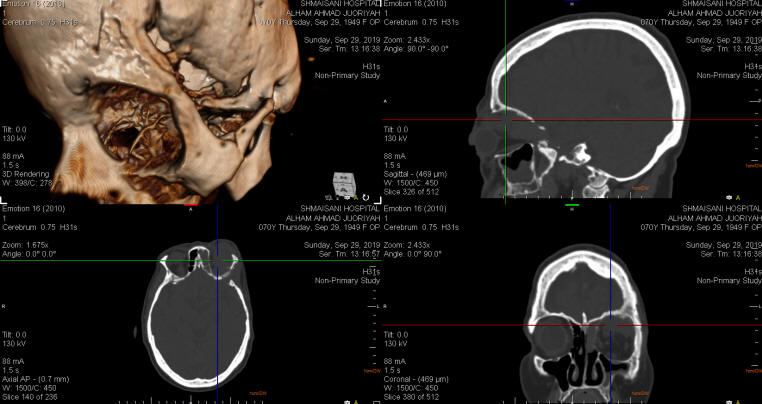

30-SEPTEMBER-2019  ILHAM AHMAD JURIYE  70 YEARS  AGGRESSIVE RECURRENCE OF LEFT PTERIONAL MENINGIOMA WITH INTRACRANIAL, LEFT INTRAORBITAL AND RIGHT ETHMOIDAL EXTENSION WITH BLIND LEFT EYE AND EXOPHTHALMUS.

The patient was operated by me 26-November-2012 for left pterional meningioma with gross practical radical resection of the tumor. MRI done 20-March-2013 confirmed total resection of the tumor with sinusitis of the frontal area left side. The patient then came 02-December-2013, telling that she still having hyperlacrimation of the with slight edema of the lateral part of the superior wall of the orbit. The patient was sent for investigations and MRI done 02-December-2013 showing the sinusitis with a carpet of meningioma at the superior wall of the left orbit. The patient was advised to repeat investigations after 3 months. The patient then came 23-June-2014 with progression of the exophthalmus left eye and hyperlacrimation. The left pupil is reactive, but more wide than the right and she can see  with normal OMNs function. MRI done the same day showing considerable recurrence of the meningioma behind the left orbit and she was advised to undergo surgery for this mass. The patient disappeared and came came to the clinic 07-August-2019 telling that she is blind in the left eye for 4 years with pronounced left exophthalmus and decreased mobility of the eye movements to all directions. MRI performed 27-June-2019 showing small intradural compartment over the left frontal area and huge intraorbital tumor 52x33x25.6 mm pushing the globe downward with the optic nerve and other compartments involving the left ethmoidal area.

The patient was sent for cardio evaluation and new MRI performed 20-august-2019 ruling out involvement of the carotids.

CT-scan with 3D reconstruction with bone defects after the first surgery.

Coronal MRI showing the involved left orbit.